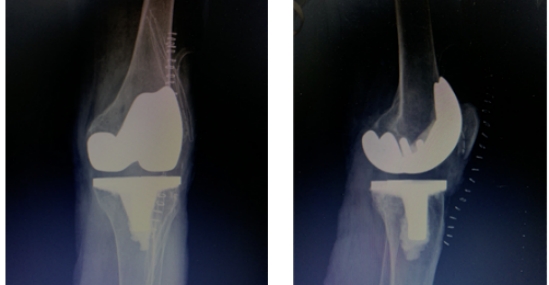

3月8日,哈尔滨医科大学附属第一医院群力院区骨科王文波教授团队应用术中便携式导航髓外定位截骨技术,成功为一名双侧严重弓形股骨的女性不开髓精准置换全膝关节,术后第二天患者便顺利下地行走。

53 岁的平女士多年来一直被膝关节疼痛所困扰,近来疼痛加重,影响正常直立行走,遂找到王文波求治。王文波检查发现患者存在严重的双侧弓形股骨,无法进行髓内定位,常规膝关节置换方式无法完成手术,决定采用便携式导航定位技术,采用术中髓外定位方式,为平女士精准定位截骨完成全膝关节置换手术。

经过术前详尽的规划预演,王文波团队在术中导航系统的辅助下,仅花费一个小时便顺利完成手术。术后患者感觉疼痛明显减轻,第二天便下地行走。

王文波介绍,IKPAS全膝关节手术定位系统利用传感器技术,术中实时测量计算获得个性化的角度数据,不开髓就可帮助医生术中精准截骨,定位假体安装位置,手术伤口小,有效降低并发症的发生,患者术后体验好,缩短术后康复时间。